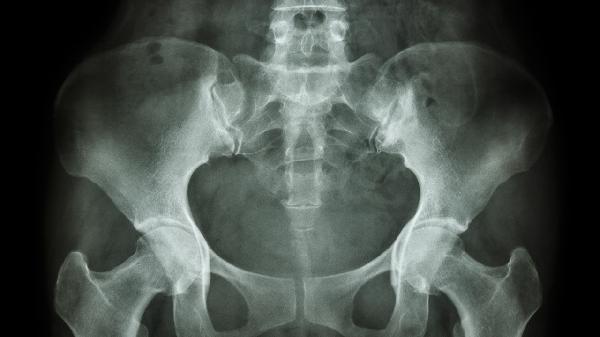

影响耻骨肌正常形态的常见疾病有哪些

影响耻骨肌正常形态的常见疾病主要有耻骨炎、耻骨联合分离、骨盆骨折、股骨头坏死和盆腔肿瘤。这些疾病可能由外伤、感染、退行性变或肿瘤压迫等因素引起,需结合影像学检查明确诊断。

日常需注意补充优质蛋白和钙质以维持骨骼肌肉健康,避免久坐或过度负重活动。出现持续骨盆疼痛、行走困难时应及时就诊骨科或妇产科,通过X线、CT等检查明确病因。康复期可在医生指导下进行盆底肌训练,使用热敷缓解肌肉紧张,但禁止自行按摩急性损伤部位。